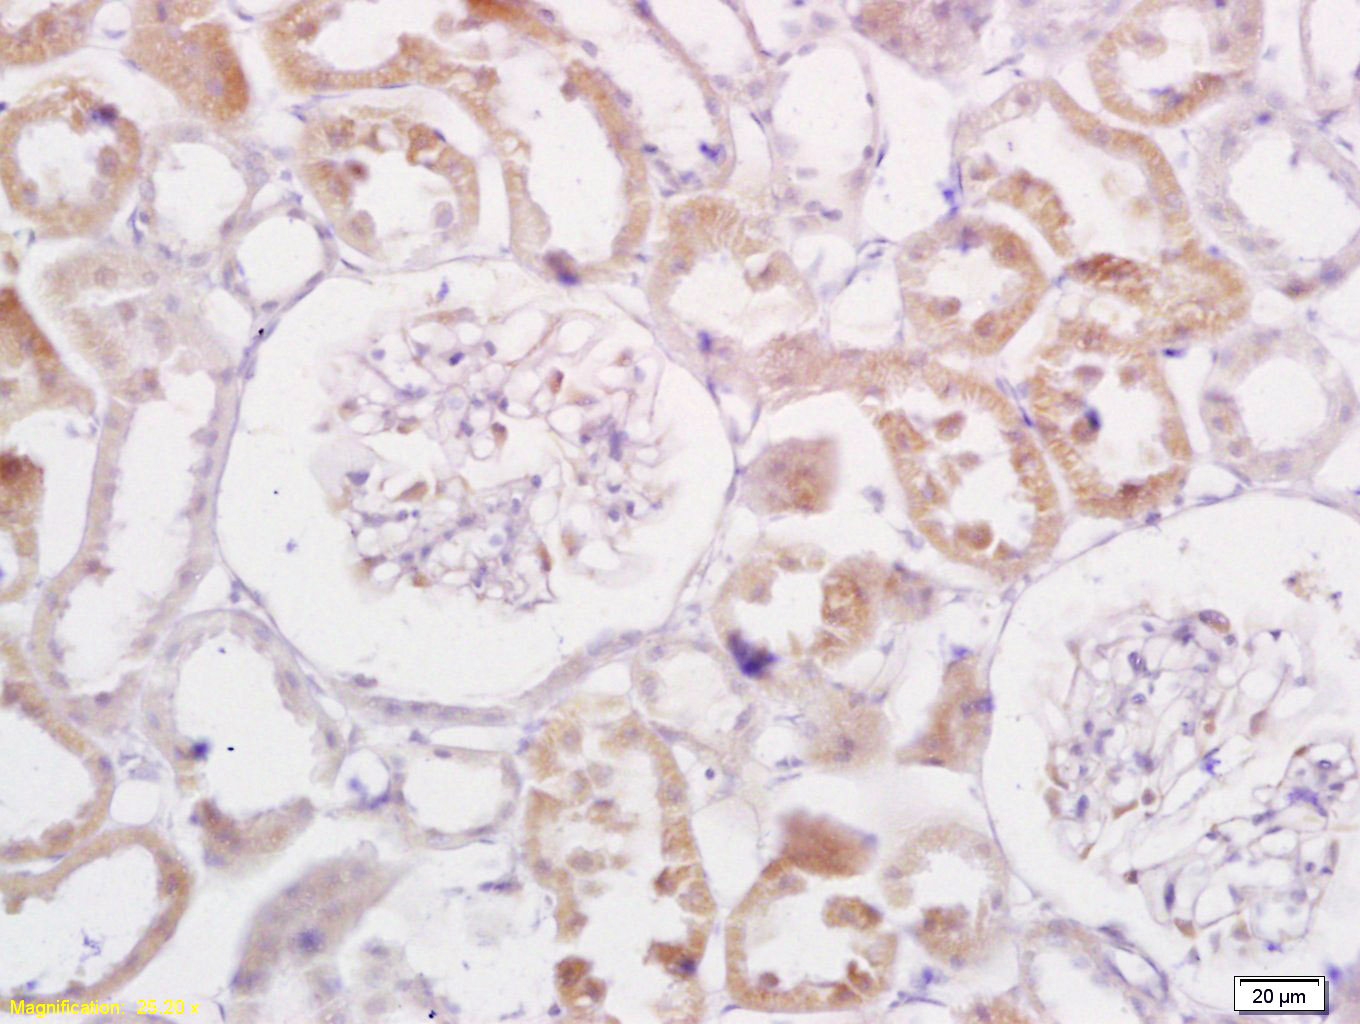

Tissue/cell: rat kidney tissue; 4% Paraformaldehyde-fixed and paraffin-embedded; Antigen retrieval: citrate buffer ( 0.01M, pH 6.0 ), Boiling bathing for 15min; Block endogenous peroxidase by 3% Hydrogen peroxide for 30min; Blocking buffer (normal goat s